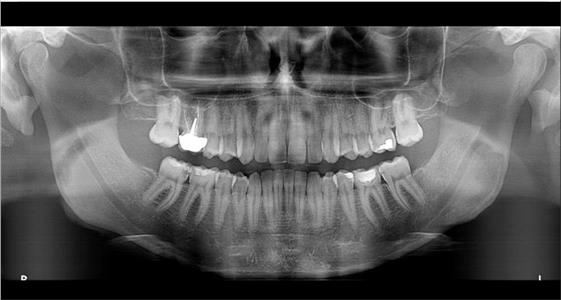

Панорамикс кабинет

За само 13 секунди се добива високо квалитетна ортопантомграфска снимка, странична смнимка, снимка на вилични зглобови, снимка на синуси. Најновиот Kodak панорамикс има 2Д+ програма со која се добиваат 5 пресека во длабочина за прецизна дијагноза и позиција на импактирани заби и други промени. Со квалитетна панорамска снимка нашиот стручен тим ќе постави точна дијагноза и одреди соодветен план на терапија.